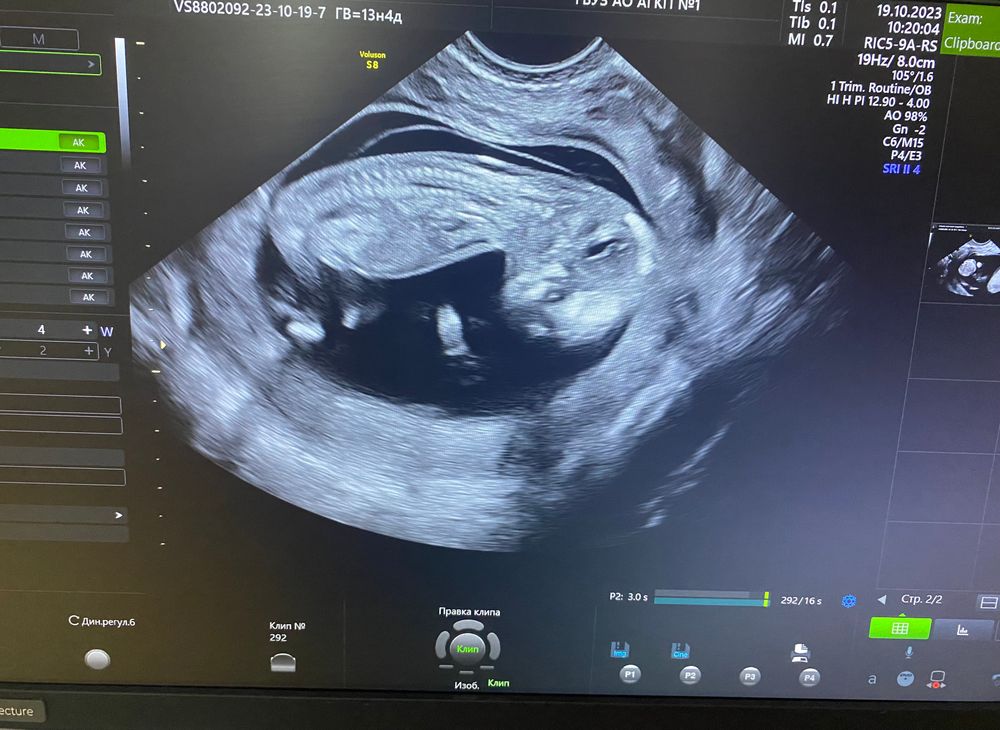

Сегодня был первый скрининг, срок по месячным 13 недель 4 дня, по скринингу 12 недель 4 дня (что и следовало ожидать, поздняя овуляция была)

КТР 62 мм, ТВП 1,8 мм, ЧСС 167 ударов, носовая кость - визуализируется, норма.

ручки, ножки, голова,желудок все в норме🙏🏼🙏🏼🙏🏼

Прикрепление по передней стенке😀

Врач сказала, что слава богу малыш отдыхал пока замеры делали, потом начал ножками отталкиваться, ручками махать, сказали очень активный😻🙏🏼